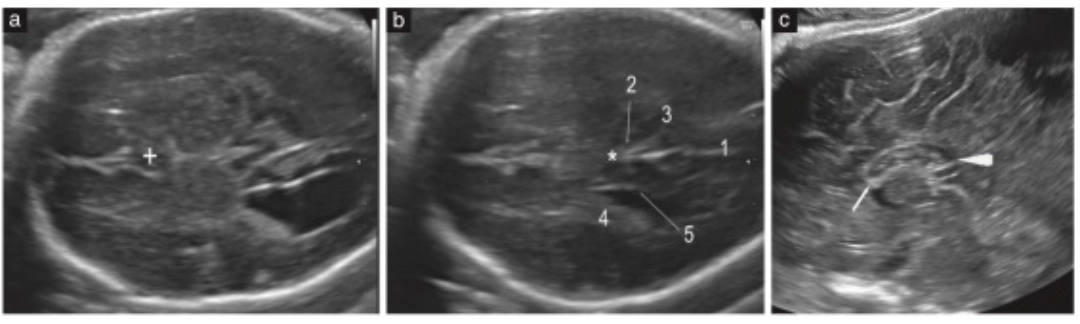

Ecografía transabdominal y transvaginal de un feto sano a las 22 semanas. Se observan estructuras normales del complejo anterior (CSP bien definido, astas anteriores con forma de coma) y del complejo posterior (surco calloso visible, CC cruzando la línea media). Fuente: Viñals et al., 2025.

Lo más relevante: todos estos signos fueron detectados con ecografía transabdominal, en planos axiales estándar, y usando equipos Voluson.